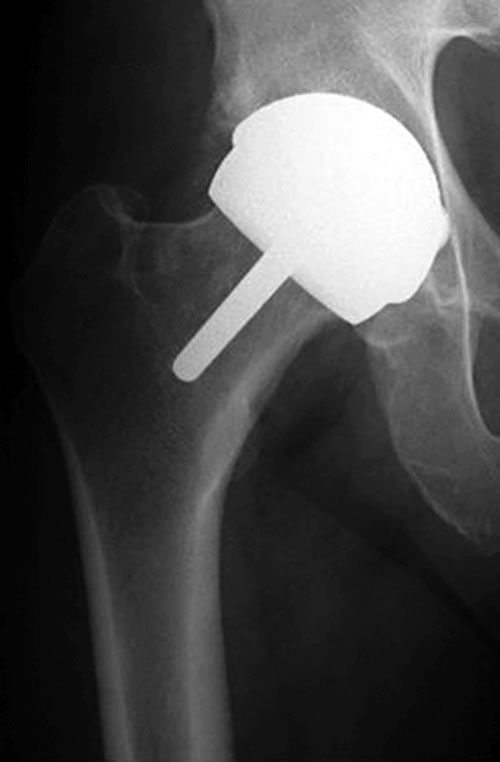

During the resurfacing procedure, your doctor creates an incision. This allows them to access the hip and thigh bone. Then, they trim down the head of the femur and put a metal covering over it. Lastly, the surgeon removes any damaged bone pieces from the joint and replaces them with metal shells.

Although resurfacing is a type of hip replacement, it differs in significant ways. The hip replacement surgery that many people think about involves removing the entire femoral head. During a regular hip replacement, the surgeon replaces the socket of the hip bone with a completely new one rather than putting a metal cap on the original.

Hip resurfacing is the process of removing damaged bone and cartilage from the hip joint. On top of the reduced thighbone, your surgeon installs a smooth metal cover. The hip socket is lined with a metal casing. These two metal components move in tandem, providing for smooth, painless action.

Think of the top portion of the femur as your neck and head. Hip resurfacing is more like trimming your hair and then putting a hat on. Meanwhile, hip replacements are more like removing the head and replacing it with a new one.

Hip replacement is as it sounds – a replacement of something. The surgeon removes the head of the femur and replaces it with a metal component of a similar shape. During resurfacing, however, the head of the femur is simply shaved down to take away the damaged parts.

The surgeon removes the femoral head from the hip socket joint. Then, they trim it with special surgical tools and place a metal cap over the top. After that, they remove damaged cartilage and bone from the area.

They push a metal cup into the socket, place the femoral head back inside, and finally close the incision surgically.